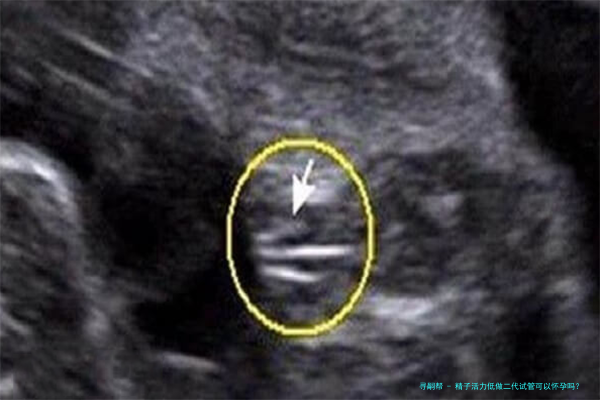

显微受精技术技术是在第一代试管婴儿技术基础上发展起来的一种更加邃密的操作方法。它通过显微操作技术,将单纯精子直接注入到卵子里面,进而达成受精过程。这一类方法绕开了精子自然穿透卵子的障碍,显著提高了受精率和胚胎发育的质量,尤其适宜于精子比较少、活力低或模样异常的患者。

四、ICSI操作:将筛选出的精子通过显微操作技术直接注入卵子里面。